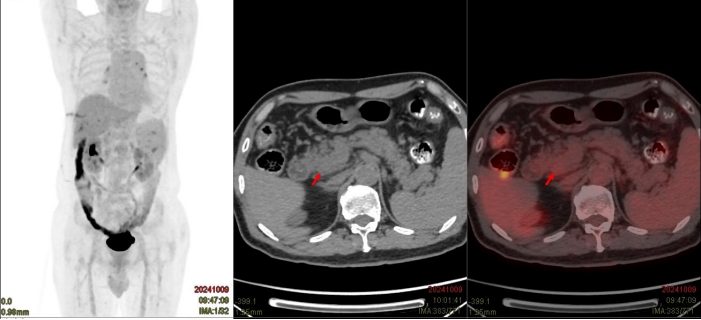

患者为57岁女性,因“反复左上腹痛1月余”入院,入院后完善PET-CT等影像学检查示胰腺沟突大小约2cm×2cm结节,FDG代谢增高,胰腺头颈部巨大囊性灶并壁结节,大小约9cm×7cm×7cm,FDG增高,胰腺体尾部萎缩,考虑为胰腺黏液性囊性肿瘤并恶变。

PET-CT示胰腺沟突结节,胰腺头颈部巨大囊性灶并壁结节,胰腺体尾部萎缩。两者FDG代谢均增高,考虑为胰腺黏液性囊性肿瘤并恶变可能